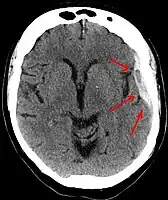

Subdural hematomas occur most often around the tops and sides of the frontal and parietal lobes.[9][10] They also occur in the posterior cranial fossa, and near the falx cerebri and tentorium cerebelli.[9] Unlike epidural hematomas, which cannot expand past the sutures of the skull, subdural hematomas can expand along the inside of the skull, creating a concave shape that follows the curve of the brain, stopping only at dural reflections like the tentorium cerebelli and falx cerebri.

Chronic subdural after treatment with burr holes

On a CT scan, subdural hematomas are classically crescent-shaped, with a concave surface away from the skull. However, they can have a convex appearance, especially in the early stages of bleeding. This may cause difficulty in distinguishing between subdural and epidural hemorrhages. A more reliable indicator of subdural hemorrhage is its involvement of a larger portion of the cerebral hemisphere. Subdural blood can also be seen as a layering density along the tentorium cerebelli. This can be a chronic, stable process, since the feeding system is low-pressure. In such cases, subtle signs of bleeding—such as effacement of sulci or medial displacement of the junction between gray matter and white matter—may be apparent.